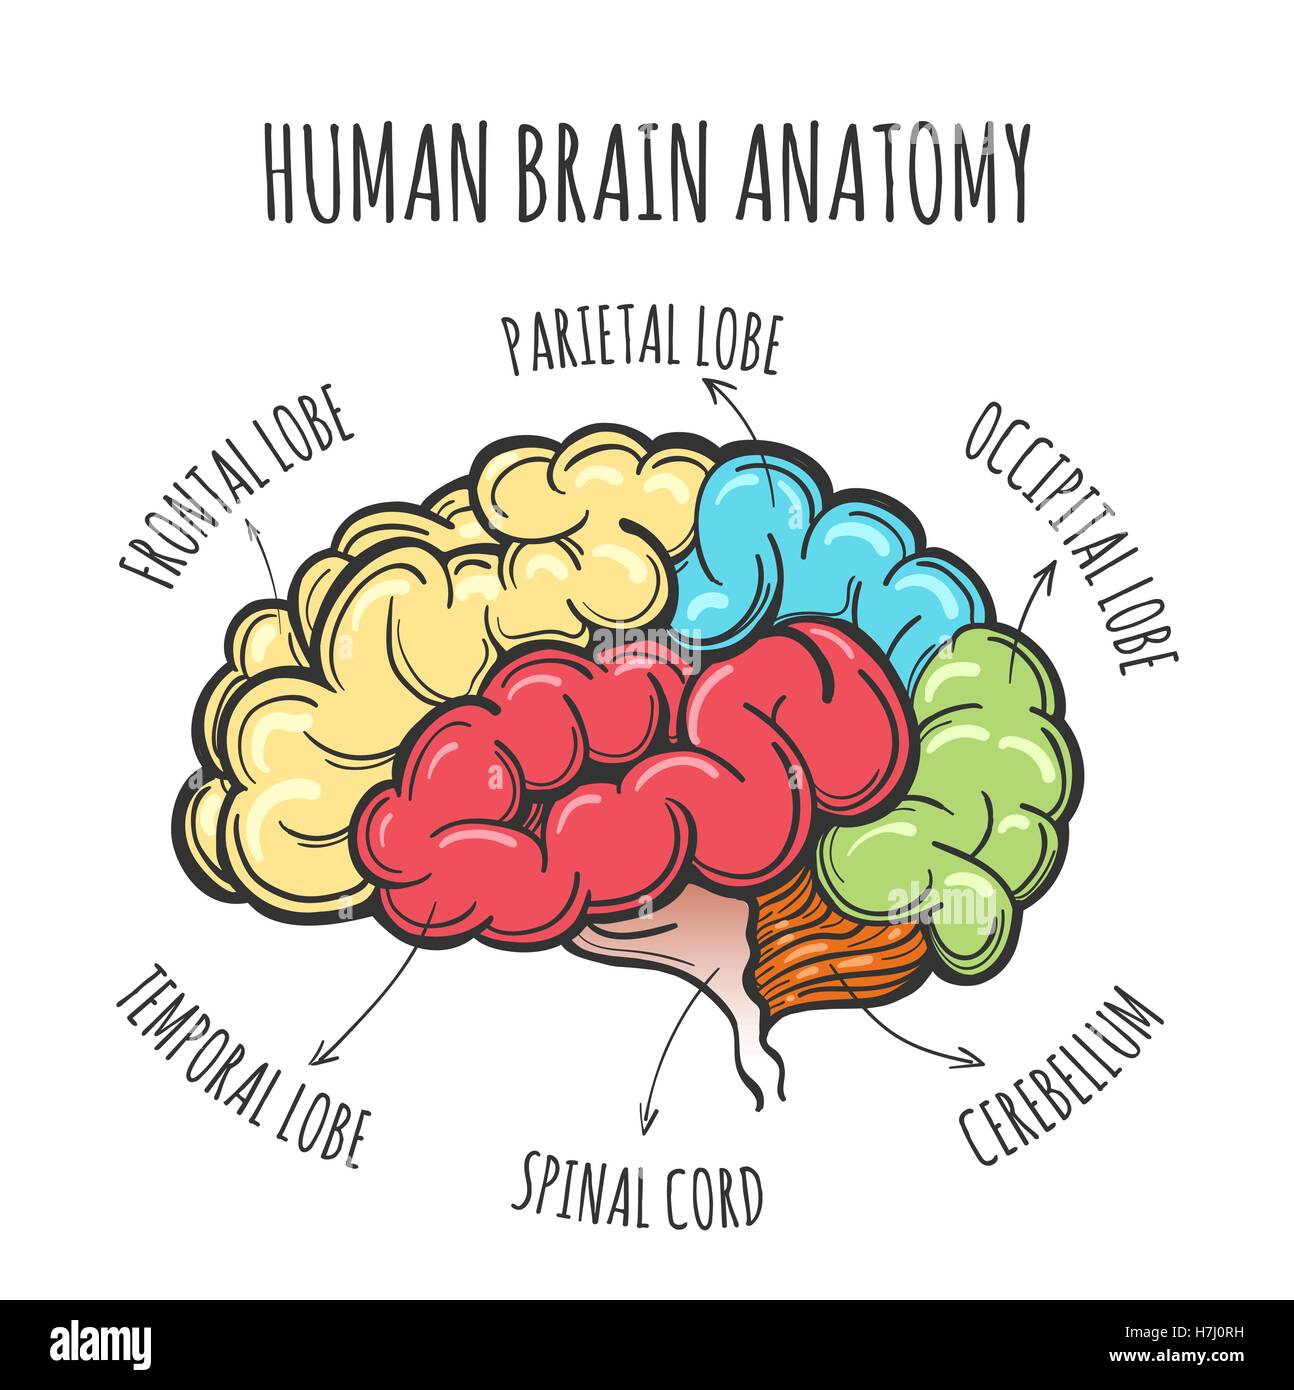

RFH7J0RH–Parti principali del cervello umano. Cervello umano nel disegno stile. Illustrazione Vettoriale

RFRPYAGD–Struttura del cervello umano. Testa umana con all'interno del cervello. Cervello umano parti principali. Illustrazione Vettoriale.

RF2R1KGAT–Struttura cerebrale umana. Emisferi e lobi della corteccia cerebrale. lobi frontali, temporali, occipitali e parietali. vista laterale e superiore